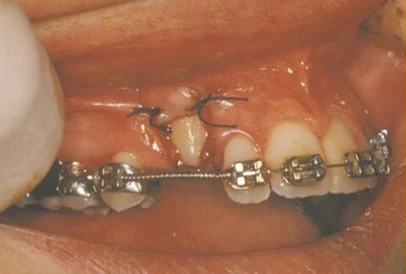

In a simple surgical procedure performed in the surgeon’s office, the gum on top of the impacted tooth will be lifted up to expose the hidden tooth underneath. If there is a baby tooth present it will be removed at the same time. Once the tooth is exposed, the oral surgeon will bond an orthodontic bracket to the exposed tooth. The bracket will have a miniature gold chain attached to it. The oral surgeon will guide the chain back to the orthodontic arch wire where it will be temporarily attached. Sometimes the surgeon will leave the exposed and impacted tooth completely uncovered by suturing the gum up high above the tooth, or making a window in the gum covering the tooth. Most of the time the gum will be returned to its original location and sutured back with only the chain remaining visible as it exits a small hole in the gum.

Shortly after surgery (1-14 days) the patient will return to the orthodontist. A rubber band will be attached to the chain to put a light eruptive pulling force on the impacted tooth. This will begin the process of moving the tooth into its proper place in the dental arch. This is a carefully controlled, slow process that may take up to a full year to complete. Remember, the goal is to erupt the impacted tooth and not to extract it. Once the tooth has moved into the arch in its final position, the gum around it will be evaluated to make sure it is sufficiently strong and healthy to last for a lifetime of chewing and tooth brushing. In some circumstances, especially those where the tooth had to be moved a long distance, there may be some minor “gum surgery” required to add bulk to the gum tissue over the relocated tooth so that it remains healthy during normal function. Your dentist or orthodontist will explain this procedure to you if it applies to your specific situation.